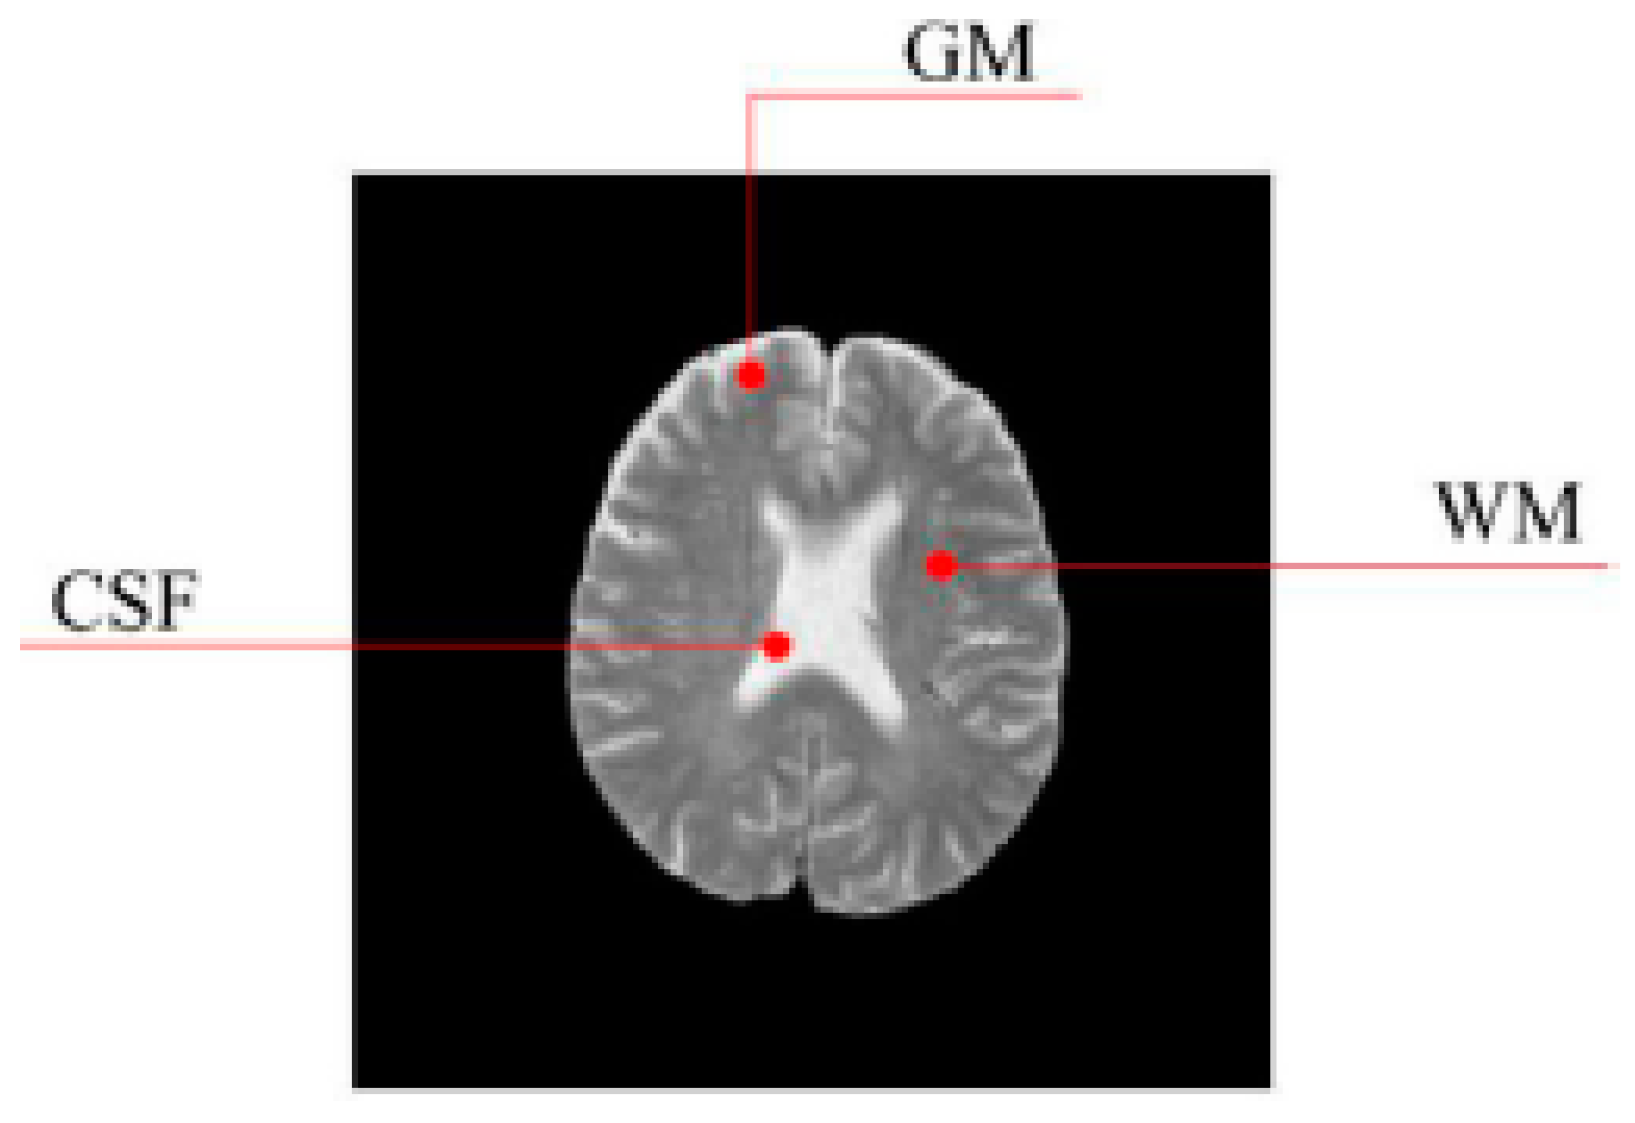

In this work, a DNA-GA optimized Tsallis [21] entropy and kernel SVM have been implemented for the classification of brain tumors as benign or malignant, which is called DNAGA-TE+KSVM. The features used for this approach were the gray matter (GM), white matter (WM) and cerebral spinal fluid (CSF) probability map, which are shown in Figure 1. Adding the WM and CSF to the features can improve the results of the method of grouping voxels into ROIs by packaging labeled atlas. These features are extracted with the help of Discrete Wavelet Transforms (DWT) [22] and Tsallis entropy. The DNA-GA algorithm is used to search a set of good parameter values in the Tsallis entropy and Gaussian radial basis function kernel. The algorithm in this paper can quickly get good parameter values and improve the classification performance of the SVM. The five-fold cross-validation is used to protect the classifier from overfitting. Once the features are extracted they are classified with the help of a trained SVM classifier.

In this paper, we used two types of images. One type of data comes from the Simulated Brain Database (SBD). MRI images can be downloaded from this database. Another kind of image is real an MRI image downloaded from the website of Harvard Medical School. In our experiments, we only retained three main brain tissues, including GM, WM and CSF, but there were skulls and other tissues in the original image.

Figure 1. Distribution of CSF, GM and WM in brain tissues.